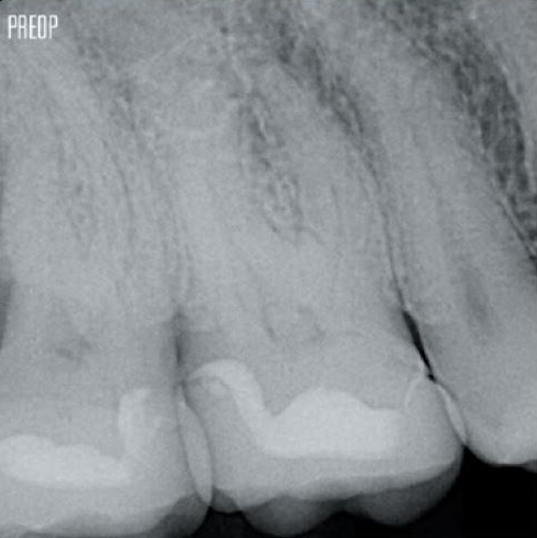

Korunan dentin sayısında artış. Uygun şekillendirme, yıkama ve obtürasyon sağlanır.

Fotoğraflar Dr. Ahmed Salman'ın izniyle kullanılmıştır